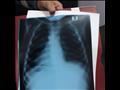

يقول طبيب بوحدة العناية في مستشفى أشمون العام، إن الطفل "أ.م.ز" عامين ونصف، حضر إلى استقبال المستشفى يُعاني من صعوبة في التنفس وكحة شديدة، وتقرر وضع الطفل على تنفس الأكسجين ونقله فورًا إلى وحدة العناية المركزة للأطفال بمستشفى أشمون العام، لحق ذلك عمل أشعة عادية على الصدر وتبين وجود صغر في حجم الرئة اليسري و"استرواح هوائي" في الرئة اليمنى - انتفاخ-.

المشهد دفع الأطباء لعمل فحص إضافي أكثر دقة، وبالفعل أجروا أشعة مقطعية بالصبغة على الصدر، ليتبين وجود انسداد جزئي بالرئى اليمنى واحتمال وجود تضخم بالغدد الليمفاوية، لُتخيم الحيرة أكثر على الأطباء، وطلبوا مزيدًا من الفحوصات، حتى انكشفت مفاجأة غير متوقعة، حيث دخل الطفل في نوبه كحة شديدة ومتواصلة لم تتوقف، وصاحبها قيء شديد، ثم وجدوا جسم كائن حي خرج مع الكحة.